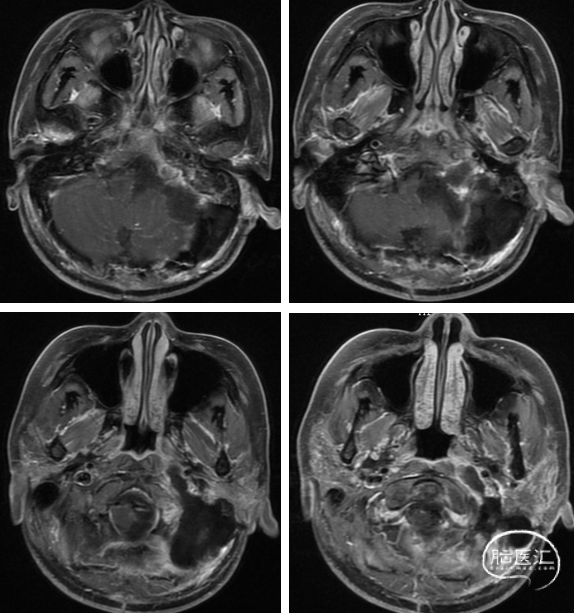

术前影像

该例患者病变位于颈静脉孔区,侵及颅内及颈部,向前达到咽旁间隙区域,多数学者都采用耳后弧形切口,Luzzi报道了38例颈静脉孔区侵及咽旁间隙肿瘤,采用George的前外侧入路,手术切口起自上项线经过乳突向下延至胸锁乳突肌前缘,胸锁乳突肌及枕后肌群整体掀起,减少了术后脑脊液漏的发生率。本例患者曾于外院行后正中切口手术,所以我们借鉴了前外侧入路的手术方式,使切口远离中线。为了更好地暴露咽旁间隙区域,进行了C1横突的磨除,但未进行椎动脉移位。

术中情况

左:乙状窦后开颅并暴露乙状窦,右:暴露颈1横突

左:磨除颈1横突,右:磨除髁旁及部分髁上骨质暴露颈静脉球及舌下神经管

左:将颈部及颈静脉孔区肿瘤贯通,右:切除颅内肿瘤

左:切除颈部咽旁间隙肿瘤,右:切除颈静脉球下方及舌下神经管内肿瘤

术后影像

术后MRI 显示肿瘤切除满意